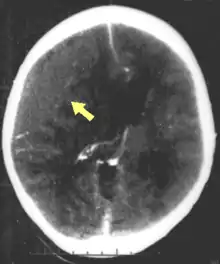

![]() | |

| CT scan showing cerebral contusions, hemorrhage within the hemispheres, and subdural hematoma. There is also displaced skull fracture of left transverse parietal and temporal bones.[2] | |